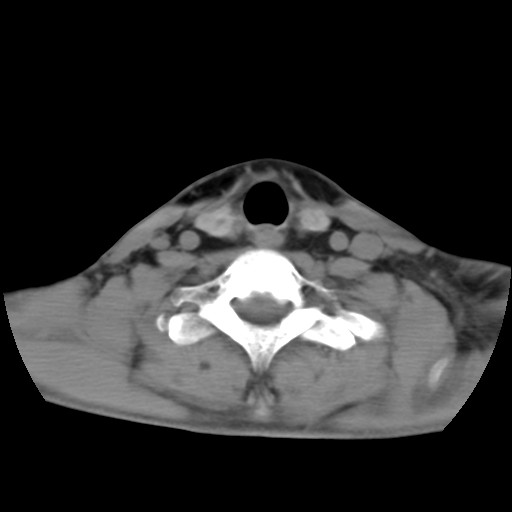

标题: CT24019:男,45岁,发现颈部肿物5个月。 [打印本页]

男,45岁,发现颈部肿物5个月,彩超示:双侧颈部及下颌部软组织增厚。

考虑双侧颈项部良性对称性脂肪增多症。